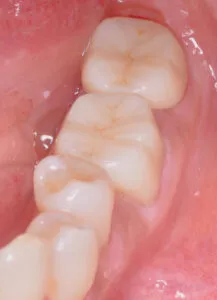

治療内容:この症例の場合保険のインレーを精密CR治療

治療費用:¥374,000(税込み)

リスク:治療直後しみることがあります。

治療回数:3回